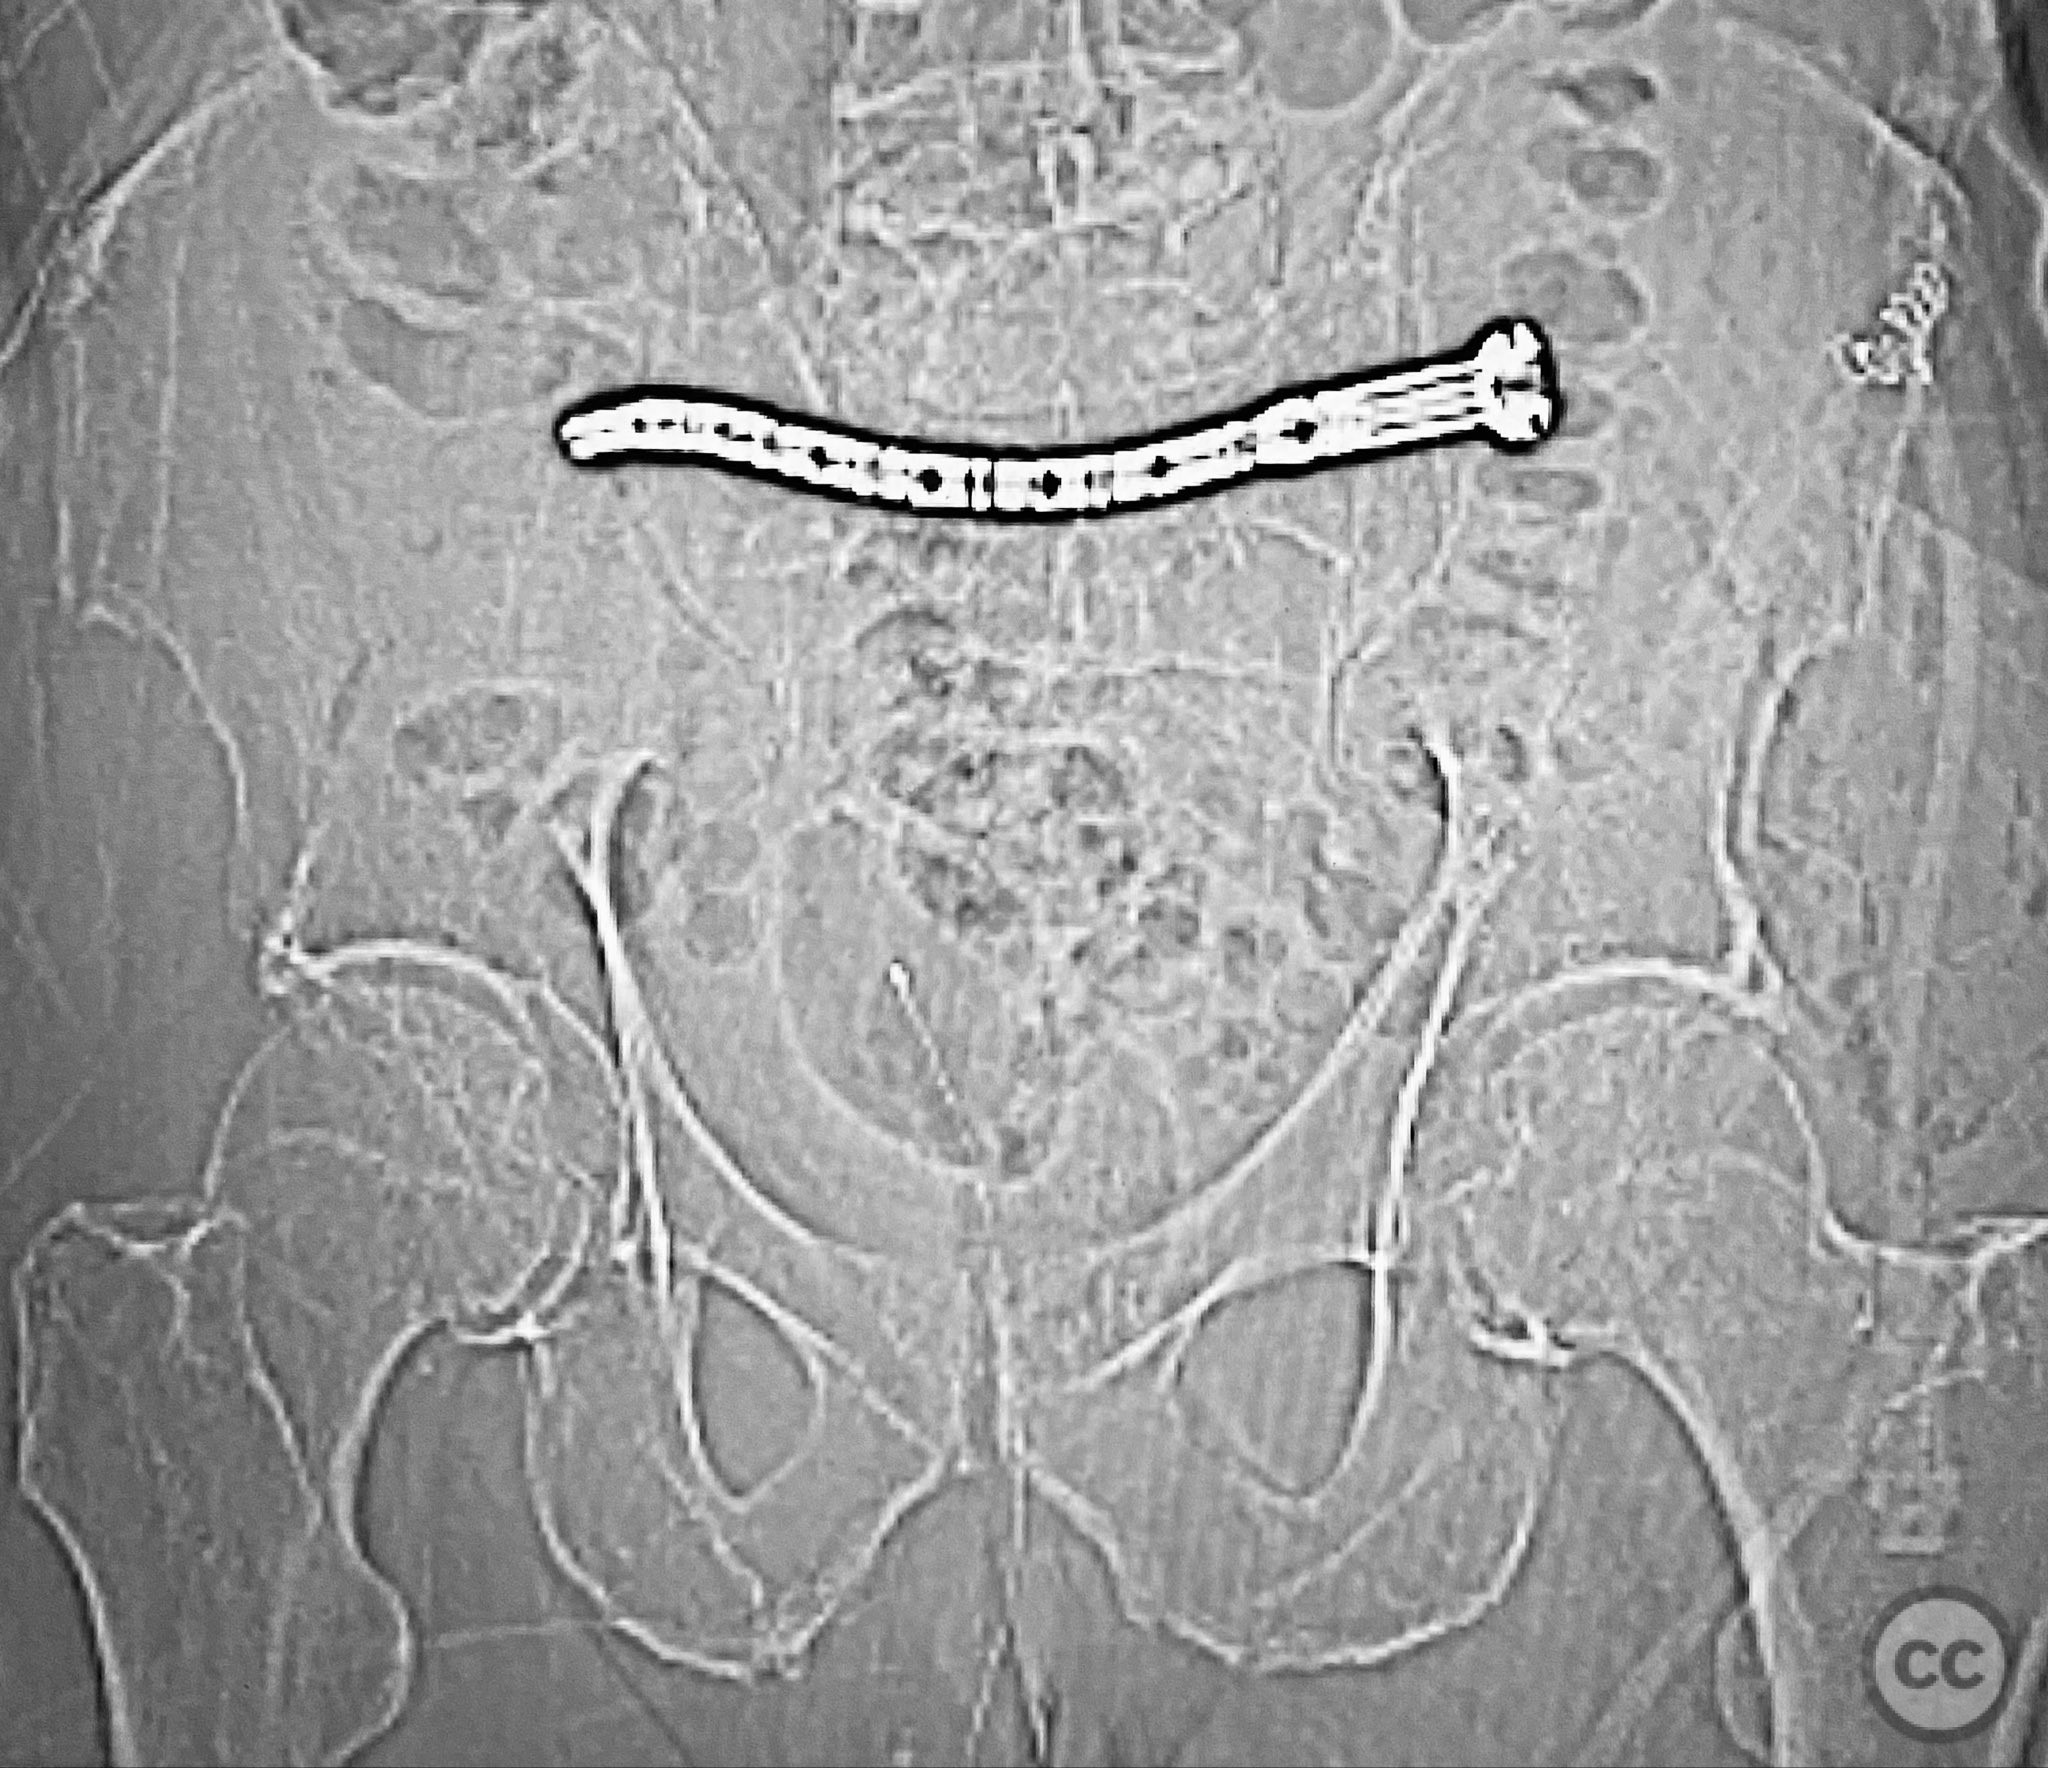

Planning remarks:  The preoperative plan involved percutaneous stabilization of the bilateral oblique upper sacral fractures using a cannulated, articulated intramedullary fixation device (CurvaFix). The anatomical approach was planned to accommodate the oblique trajectory of the sacral fracture pathways, with bilateral guide pin placement under fluoroscopic guidance, followed by device insertion and locking.

Patient positioning:  The patient was positioned supine on a radiolucent operating table to facilitate fluoroscopic imaging in multiple planes (anteroposterior, inlet, and outlet views) for accurate guide pin and device placement.

Anatomical surgical approach:  Percutaneous access was established over the dorsal aspect of the pelvis. Small incisions were made lateral to the sacrum, and soft tissue dissection was performed to the level of the os sacrum. Guide pins were advanced under fluoroscopic control along the oblique upper sacral corridors bilaterally. The cannulated CurvaFix device was inserted over each guide pin, articulated to match the oblique fracture pathway, and subsequently locked in situ according to the manufacturer’s specifications.

The articulated nature of the CurvaFix device allowed precise accommodation of the complex oblique upper sacral fracture pathways bilaterally. Percutaneous technique minimized soft tissue disruption and surgical morbidity. Postoperative CT imaging confirmed satisfactory device placement and fracture reduction. The achieved stability provided immediate pain relief, reduced or eliminated narcotic requirements, and enabled early mobilization. Surgeons with experience in device removal have reported no technical difficulties.